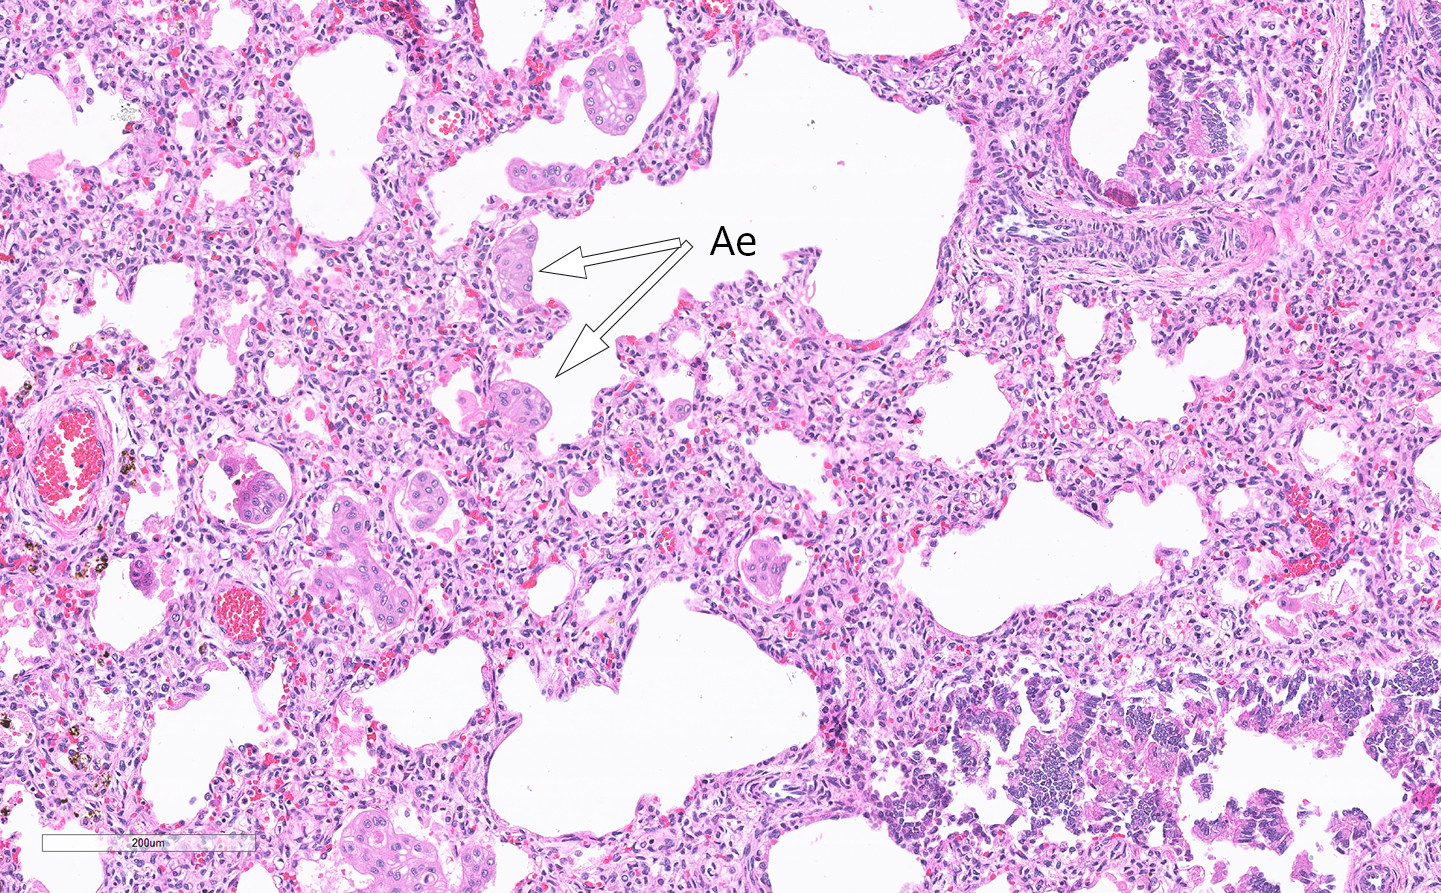

Mikroskopi fra lungene viste flak med amnionepitel som var blitt aspirert intrauterint (fig 3). Magesekken var dilatert med rikelig innhold. Pylorusområdet var fortykket. Det lot seg ikke gjøre å sondere ned til tolvfingertarmen. Miltprøve viste at det ikke forelå trisomi 13,18 eller 21.

Undersøkelse av morkaken ga ingen holdepunkter for løsning. Manglende forekomst av kjerneholdige røde blodlegemer passet med at barnets alvorlige anemi skyldtes en akutt innsettende katastrofe, en føtal blødning fra skadet navlesnorarterie. Vi tolket bildet slik at tynntarmsatresien hadde resultert i refluks av mageinnhold inn i fostervannet, noe som hadde ført til nekrose av snoren med Whartons gelé og destruksjon av nesten hele den muskulære delen av arteriene. Dette resulterte i en katastrofal føtal blødning. Tilstedeværelse av aspirert amnionepitel i barnets lunger støtter dette (fig 3). Snorens amnionepitelkledning var revet av, blitt aspirert og kunne derfor gjenfinnes i lungenes alveolære hulrom.